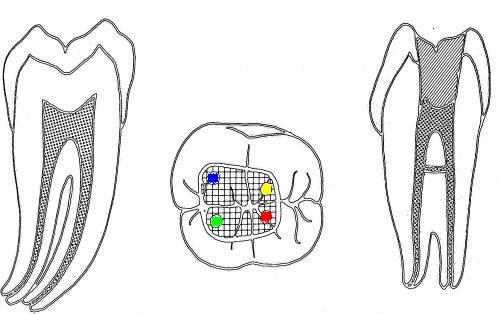

• En azul conducto mesio-vetibular

• En verde conducto mesio-lingual

• En rojo conducto distal

• En amarillo un cuarto conducto,  si el conducto distal se encuentra desplazado hacia lingual, existe una alta posibilidad de encontrar un cuarto conducto

Tres conductos en piso de cámara pulpar, el conducto distal se encuentra ensanchado en sentido buco-lingual, debe sospechar la existencia de dos conductos que comparten el orificio de entrada. Cámara intraoral X10 aumentos.

1º Molar inferior: El orificio de entrada del conducto distal se encuentra ensanchado en sentido buco lingual, debe sospechar la existencia de un cuarto conducto.

La localización  de un cuarto conducto se lleva a cabo con la técnica radiológica de Clark o por medio de una lima curvada en distal para sondear la pared lingual ó vestibular del conducto distal. Imagen inferior